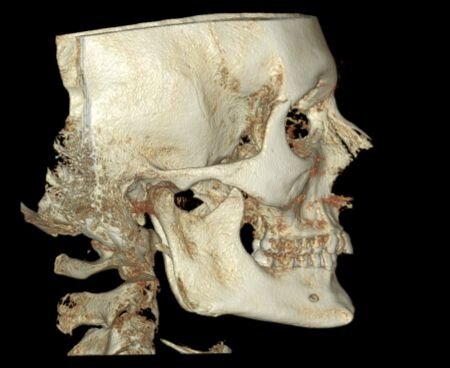

I need some advice! I have a deep and distal bite, and I've been thinking about bimax or lefort surgery, but my orthodontist said that it can be fixed with braces without surgery. The plan is to move the upper teeth slightly back and the lower teeth slightly forward to correct the bite, but I'm worried that moving the upper teeth will also move my maxilla, which is already flat. Should I be concerned about this? I want to receive valuable advice from experienced and knowledgeable individuals.

I can take any necessary measurements of the bones.

I can take any necessary measurements of the bones.